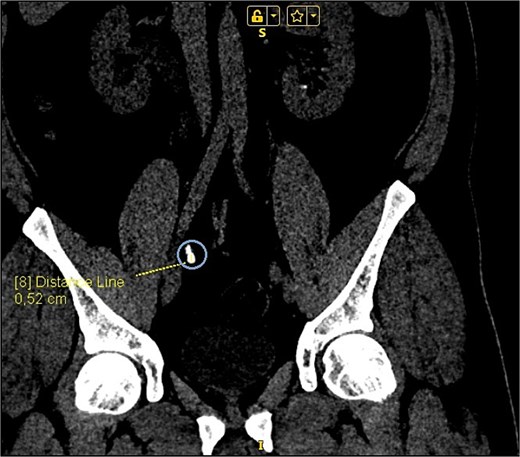

On presentation the patient reported pain in the right lumbar region, without fever starting 1 week prior to admission. The physical examination was unremarkable, except for positive right side Pasternacki's sign. Laboratory tests of full blood count, urinalysis and biochemistry were unremarkable, with the exeption of uric acid that was elevated 483 μmol/L (reference range 208–428 μmol/L) (Tables 1 and 2). Abdominal ultrasound demonstrated grade 2–3 hydronephrosis in the right kidney (Fig. 1a); a 4 mm calyceal stone, without obstruction in the left kidney. Initially, conservative therapy was started. A contrast-enhanced computed tomography (CT) scan of the abdomen and pelvis revealed bilateral calyceal nephrolithiasis and right-sided ureterohydronephrosis caused by a cluster of stones in the right distal ureter (Figs 1b, 2, and 3).

CT scan reconstruction—cluster of stones sizes, respectively, 5.2 mm, 3.2 mm, 2.8 mm—13.4 mm combined in the right distal ureter.

As a result of the CT scan, the diagnosis of spontaneous steinstrasse type 2 with complete obstruction of the right ureter was established. The patient was referred to the urology clinic where a decision was made to perform ESWL. In the following days the patient remained symptomatic with persistent hydronephrosis. Therefore it was decided that the next therapeutic step will be ureteroscopic stone disintegration. The procedure was successful and in the subsequent months, imaging studies showed no signs of hydronephrosis and the patient reported no symptoms.